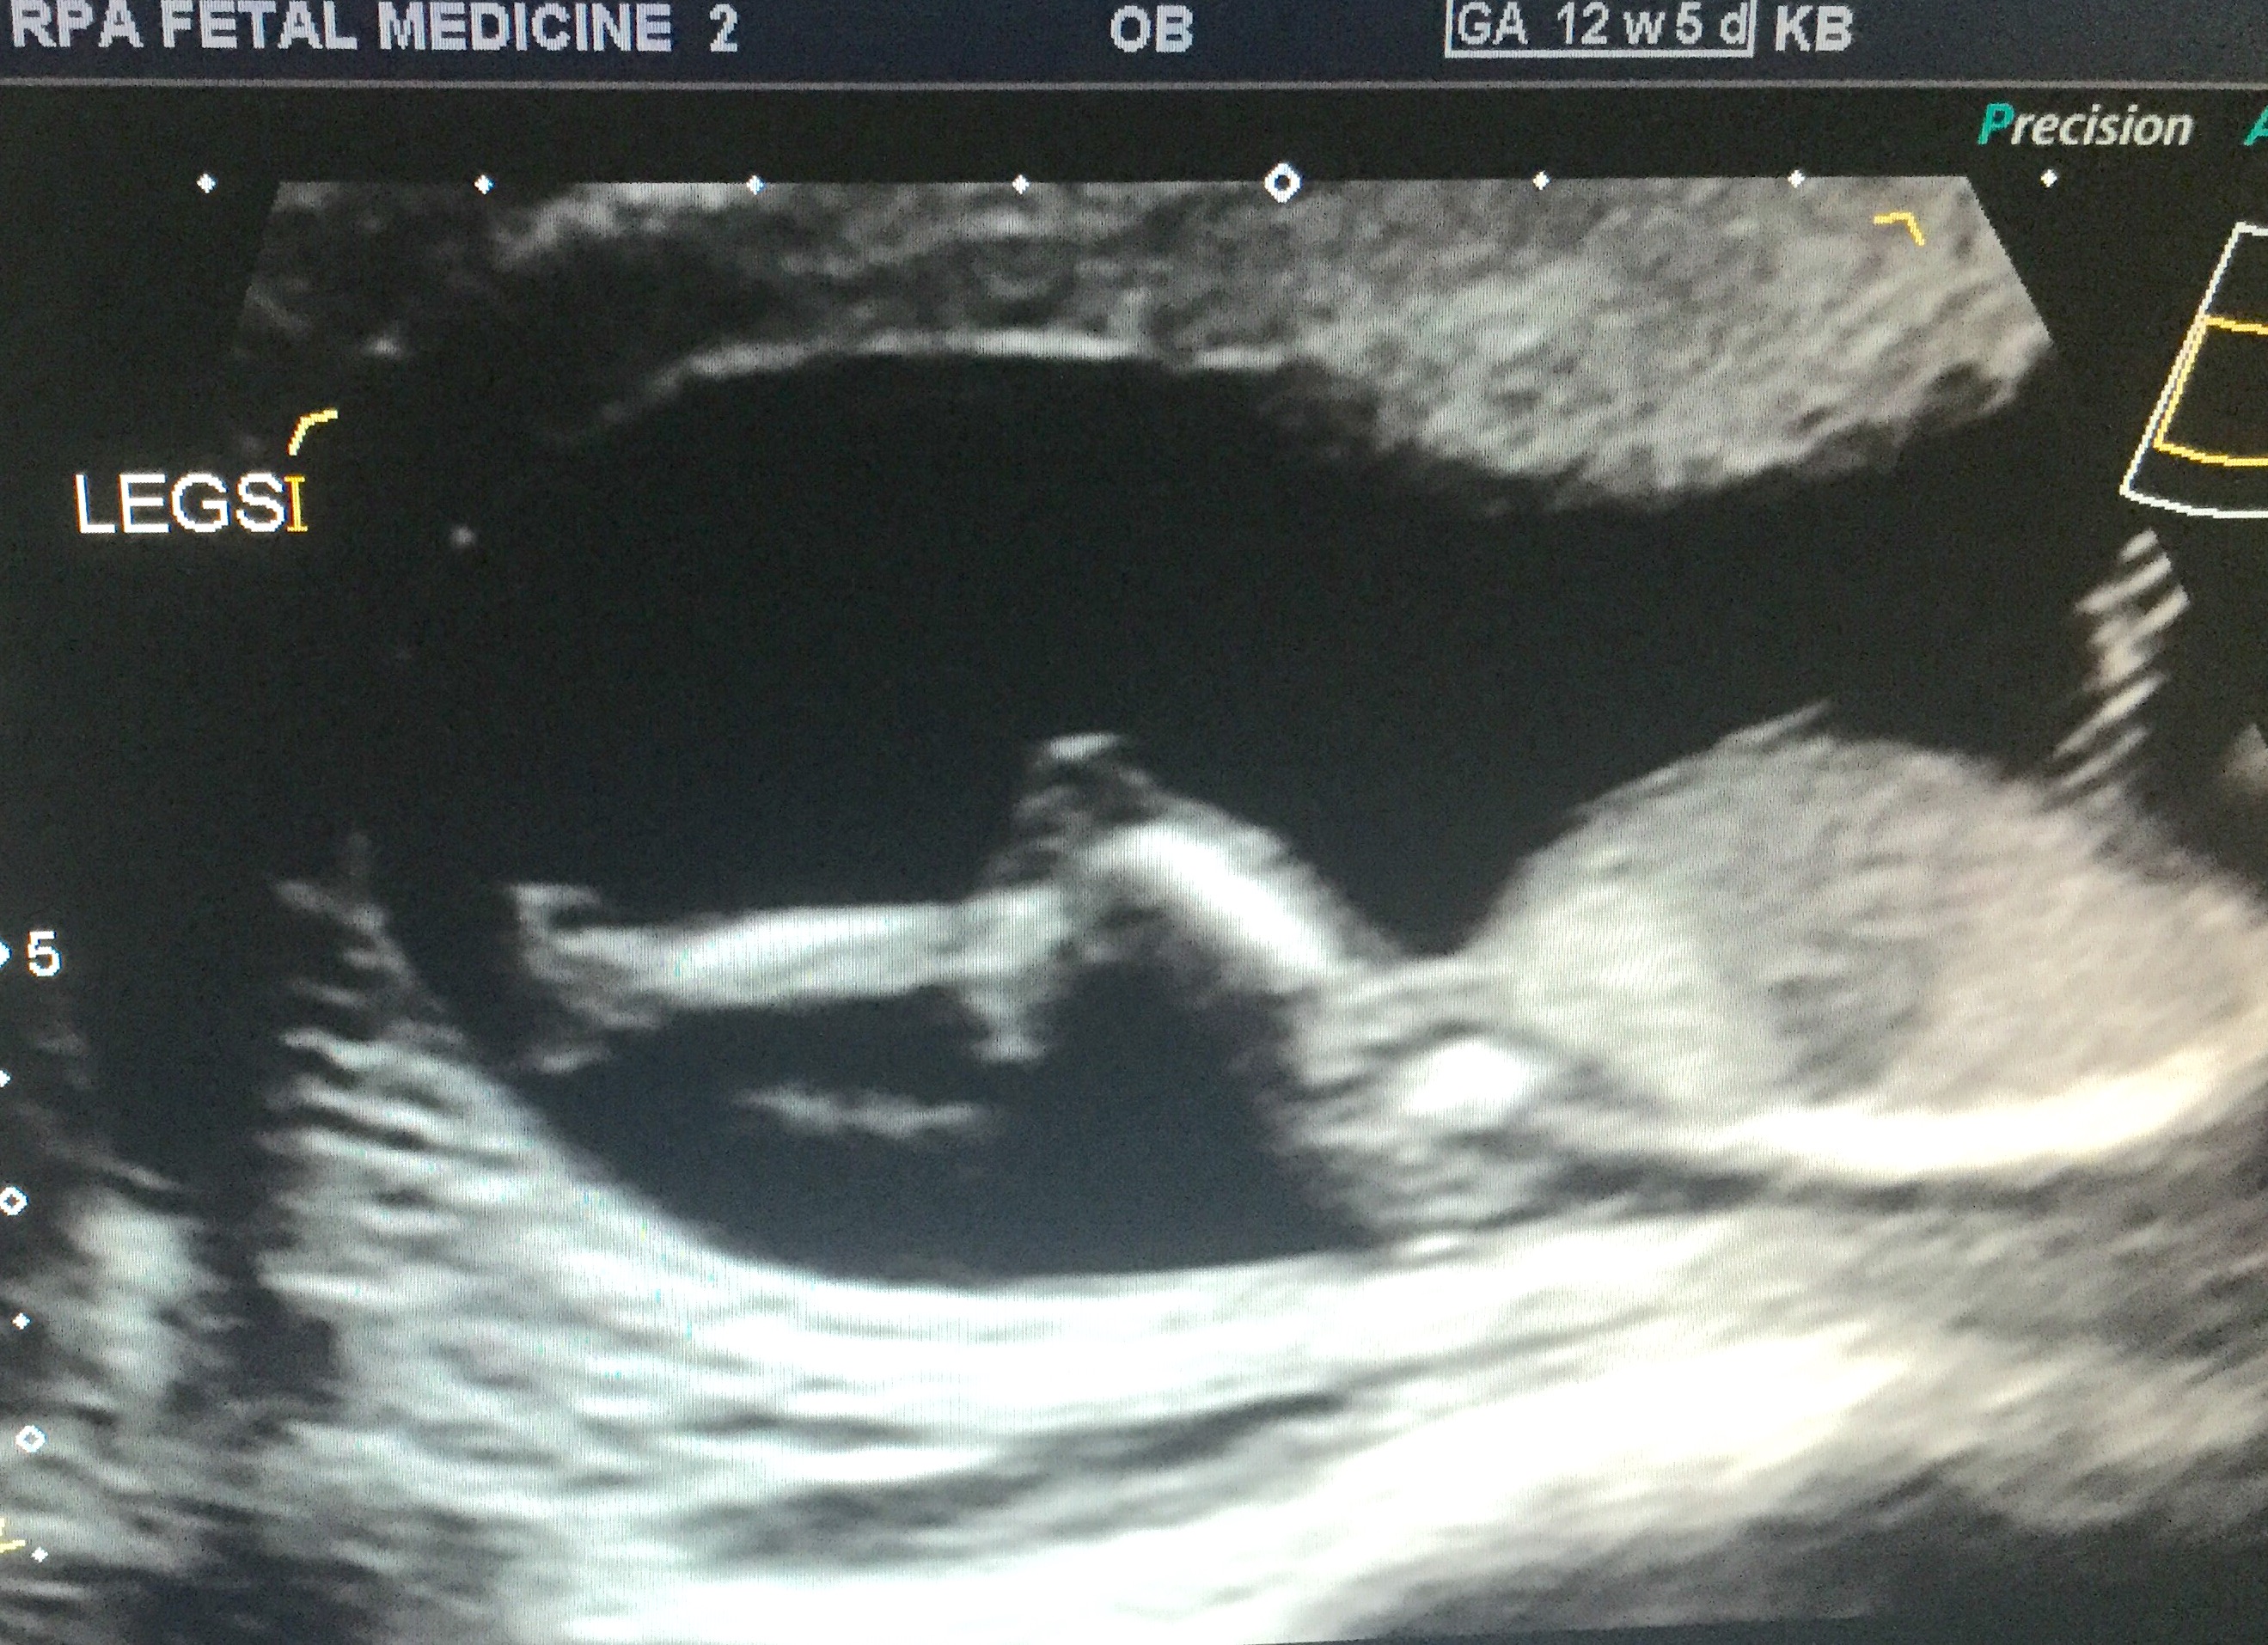

Not sure? I think I see one, if so it looks girly to me

Very slight girl lean.

Well that second pic you posted looks like a boy nub!